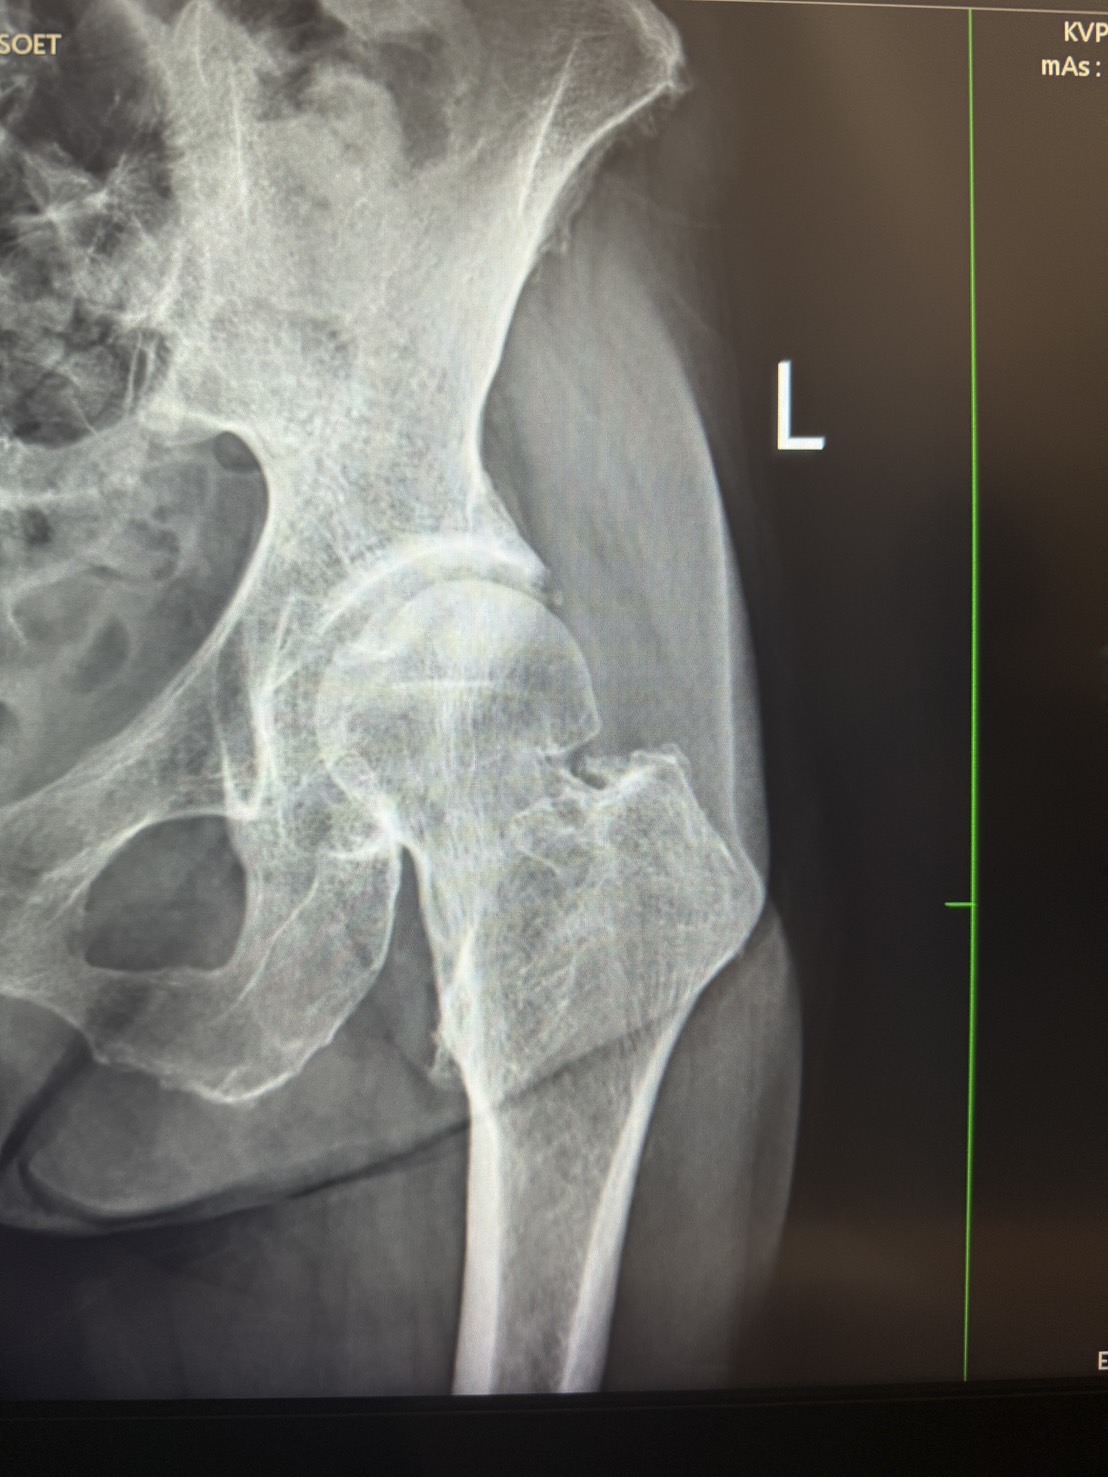

หลายคนอาจคิดว่า “หกล้มนิดเดียว ไม่น่าถึงกับกระดูกหัก” แต่สำหรับผู้สูงอายุที่มีกระดูกพรุน แม้จะล้มเพียงเล็กน้อยก็อาจทำให้ กระดูกสะโพกหัก (Hip Fracture) ได้ และนี่ไม่ใช่แค่เรื่องเล็ก ๆ เพราะอาจทำให้ เดินไม่ได้ เจ็บปวดเรื้อรัง และเสี่ยงต่อภาวะแทรกซ้อนร้ายแรง 😨

• หากกระดูกหักไม่มาก อาจใช้วิธี ยึดตรึงกระดูก (Internal Fixation) ด้วยสกรูหรือเพลท

• แต่ถ้ากระดูกหักรุนแรง โดยเฉพาะในผู้สูงอายุที่มีภาวะกระดูกพรุนมาก อาจต้อง เปลี่ยนข้อสะโพกบางส่วน (Hemiarthroplasty) หรือเปลี่ยนทั้งหมด (Total Hip Replacement - THR) เพื่อให้เดินได้ดีขึ้น